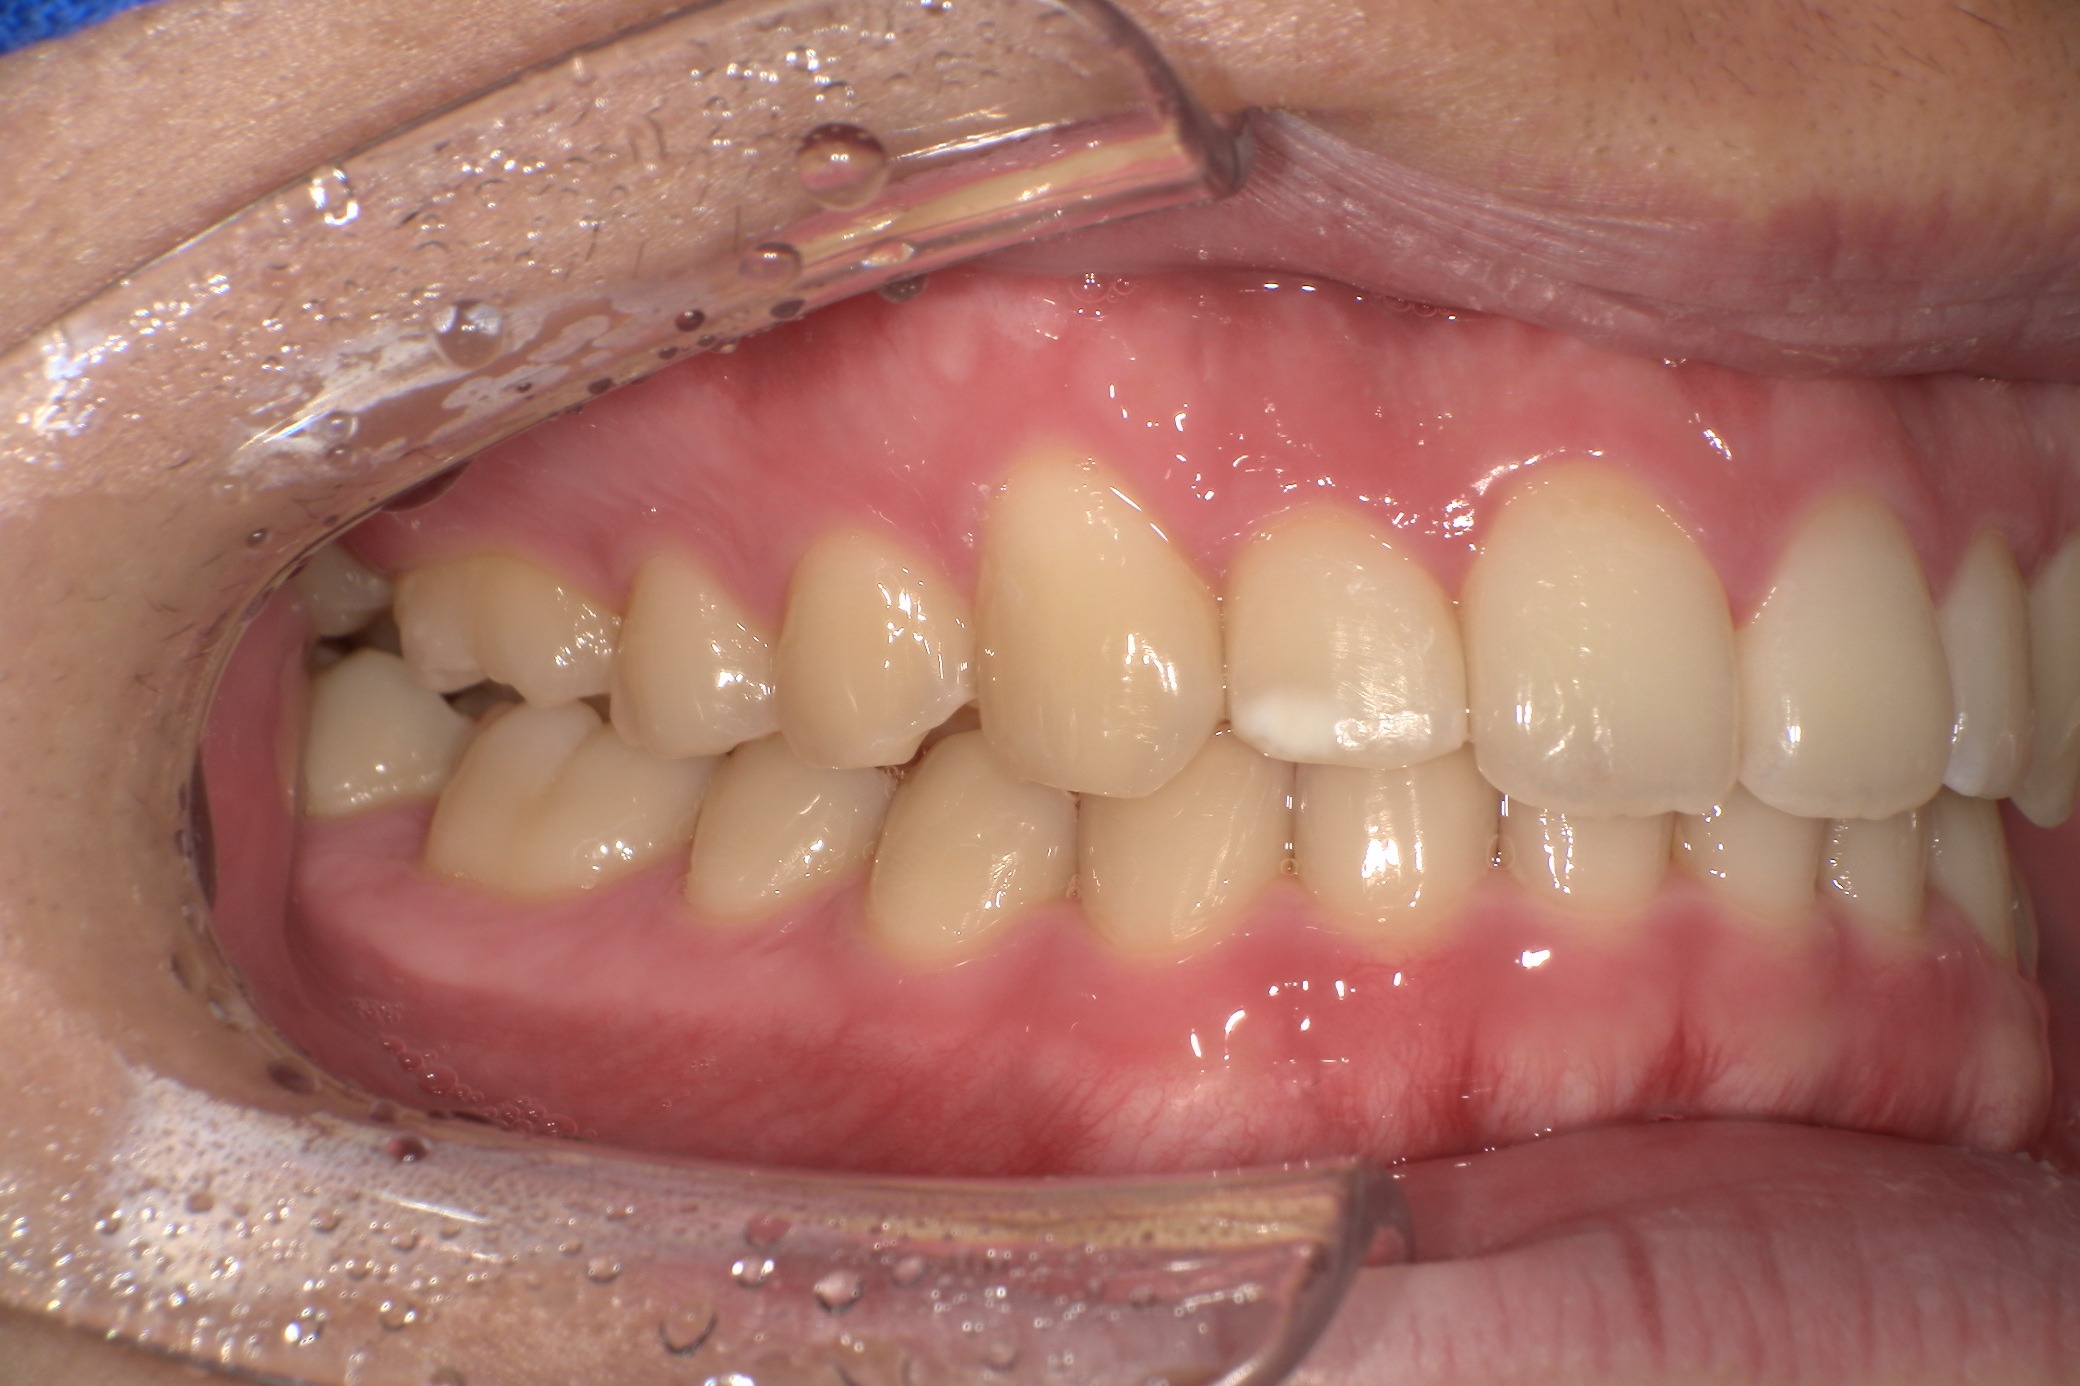

歯並びがコンプレックスで友人と写真を撮る際も気にしてしまっていたという20歳の男子大学生I.T.様にのI.T.様。始めやすい価格と目立ちにくさからスマイルモア矯正を選び、自信を持って笑えるようになった経緯を伺いました。

| 詳細情報 | |

|---|---|

| 費用 | 360,000円(税込396,000円) |

| 治療期間 | 6ヶ月 |

| 治療内容 | マウスピースを用いた歯列矯正 |

| 追加処置 | IPR |